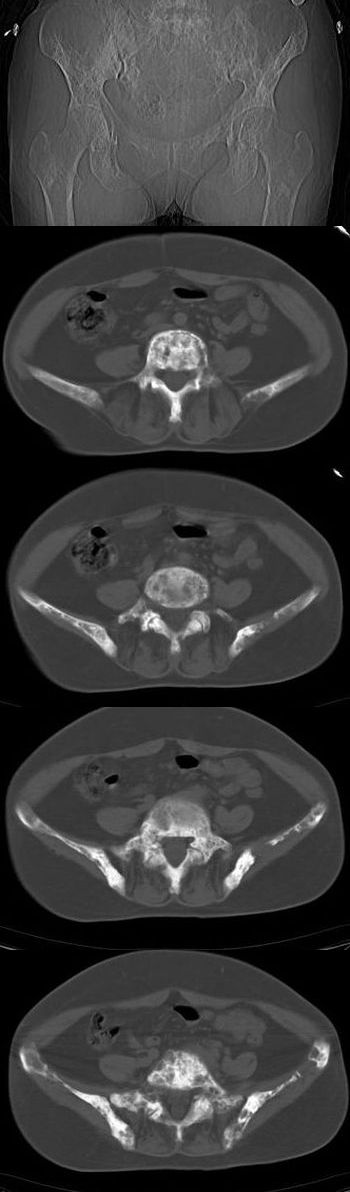

标题: CT13121:女,54岁。乳腺癌术后8年。 [打印本页]

女,54岁。乳腺癌术后8年。现感觉左腿酸困不适,并向下放散。左腿僵硬,不由自主。

典型溶骨型转移瘤。

骨盆及腰椎多发性溶骨性转移瘤.

成骨及融骨转移。

结合病史考虑乳腺癌术后多骨骨转移。

支持 骨转移瘤---混合型以溶骨为主

结合临床考虑多骨多灶性溶、成骨性转移。